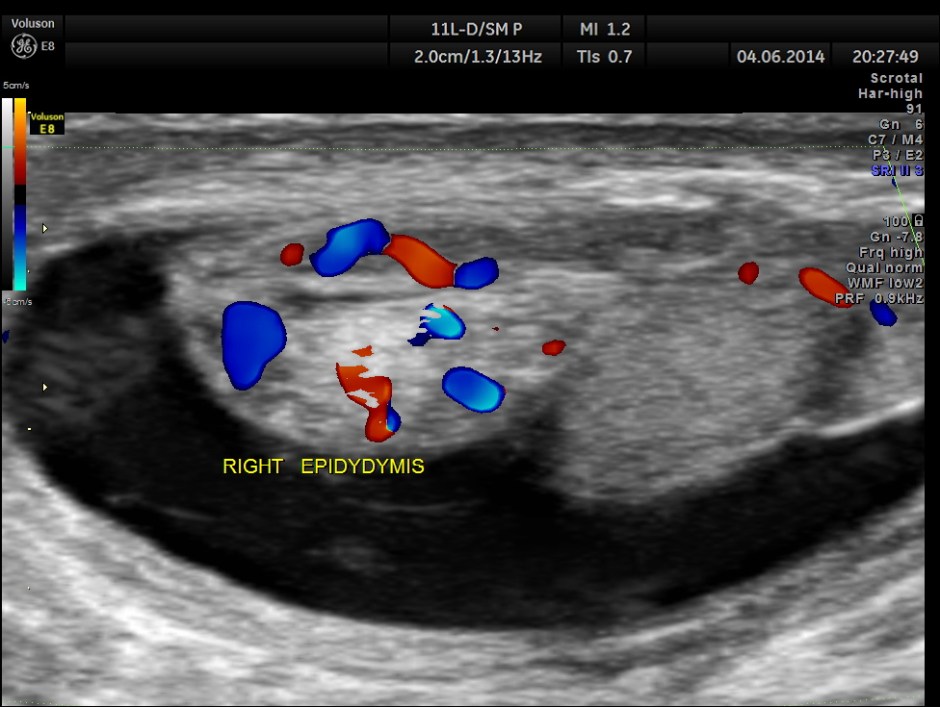

This was a 9-year-old boy , who was referred for evaluation of acute right scrotal pain of 2 days onset. He had mild right scrotal swelling and severe pain . One of the best uses of colour Doppler is for evaluation of acute scrotal pain , when the surgeon wants to rule out acute torsion . The other common condition is acute inflammation , which is medically managed. The images with colour just tell the story .

Rt Testis has normal appearance , with enlargement of the right epididymis . Colour flow imaging shows normal flow in the scrotum and increased flow in the epididymis , suggestive of acute inflammation – Acute Epididymitis.

This was a case of acute epididymitis , without orchitis . In our part of the world filarial infestation leading to acute epididymitis is a common occurrence .